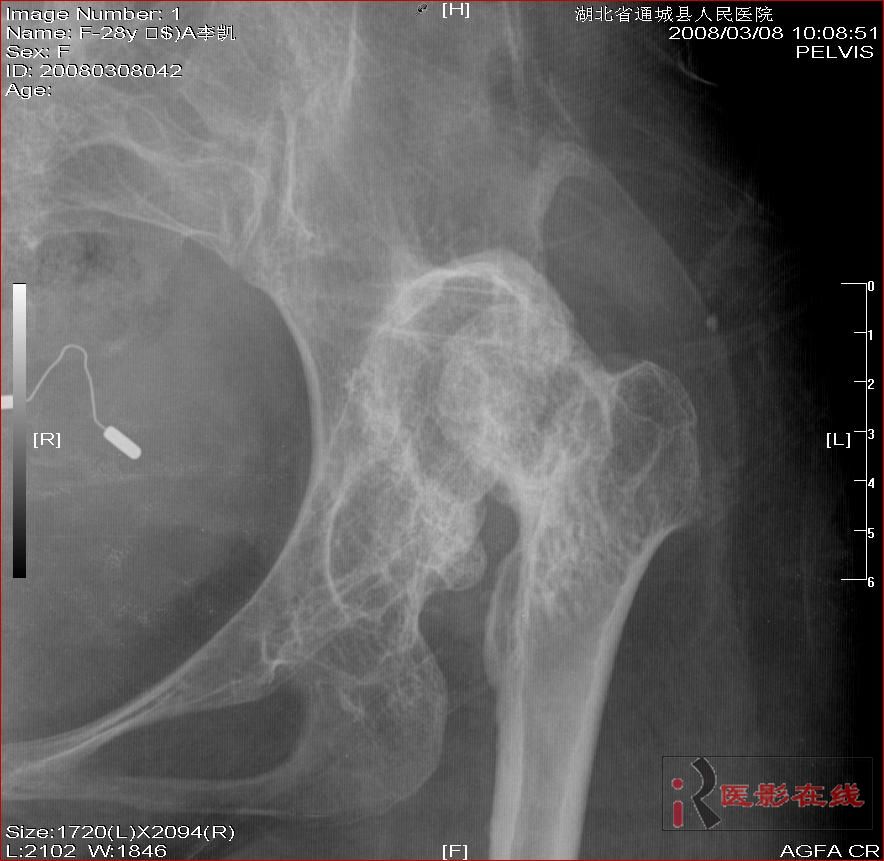

先天性双髋关节脱位自体骨关节再造

女 28岁 先天性髋关节脱位术后复查片(手术日期是2000年,数字化以前平片资料患者外带),现无其它不适,走路仍需双拐

2006年11月30日

1.双髋关节先天性脱位术后改变;2.双髋关节退行性变;3.骨质疏松(骨盆明显)。

双侧髋关节仍为脱位表现,假关节形成,部分已经强直,右股骨头碎裂,股骨干近端增粗。

结合手术史考虑:原地臼盖成形术后,髋关节退变,股骨头无菌性坏死,右股骨近端生长紊乱,骨质疏松。